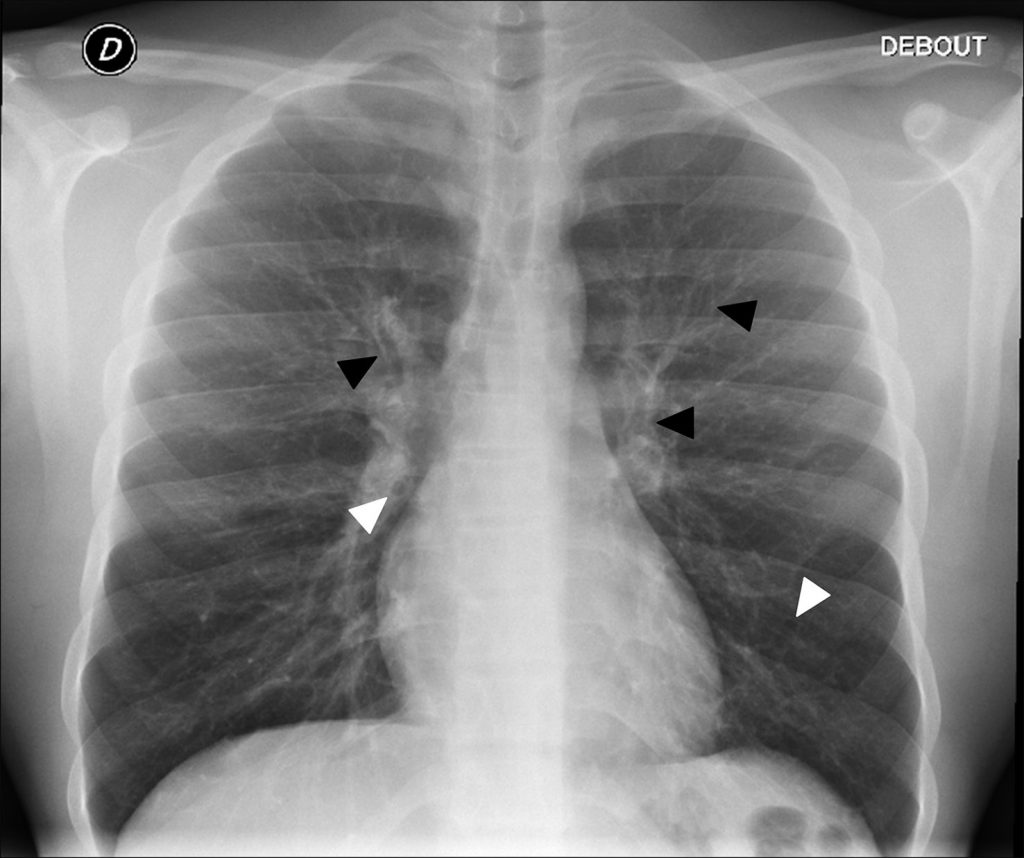

La radiographie thoracique recherche des signes d’atteinte bronchique : épaississements des parois bronchiques, bronchectasies ou dilatations des bronches se caractérisant par une augmentation de la taille des lumières bronchiques, et troubles de la ventilation (distension ou atélectasies) (figure 125.1). En cas de complication, elle recherche des impactions mucoïdes avec ou sans bronchocèles (opacités moulées dans des bronches dilatées) et des foyers de condensation pulmonaire avec des opacités de tonalité hydrique systématisées.

Fig. 125.1 Radiographie thoracique de face : mucoviscidose chez un garçon de 15 ans.

Distension thoracique (aplatissement des coupoles diaphragmatiques, visualisation des arcs antérieurs de côtes au-delà du 8e arc, hyperclarté des deux bases pulmonaires). Dilatations des bronches à parois épaisses en coupe transversale (images en « bague à chaton », flèches blanches) et longitudinales (images en rail, flèches noires).

Source : CERF, CNEBMN, 2022.